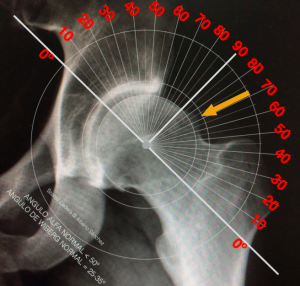

O diagnostico baseia-se numa boa e completa avaliação clínica e nos exames auxiliares de diagnóstico, devendo estes serem realizados de forma adequada e dirigida (damos relevância ao Rx em incidências próprias e adequadas e RM dirigida, 3 Tesla e com cortes radiais).